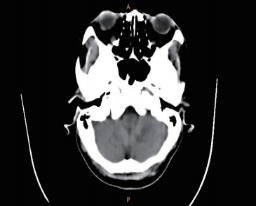

CT成(chéng)像系統